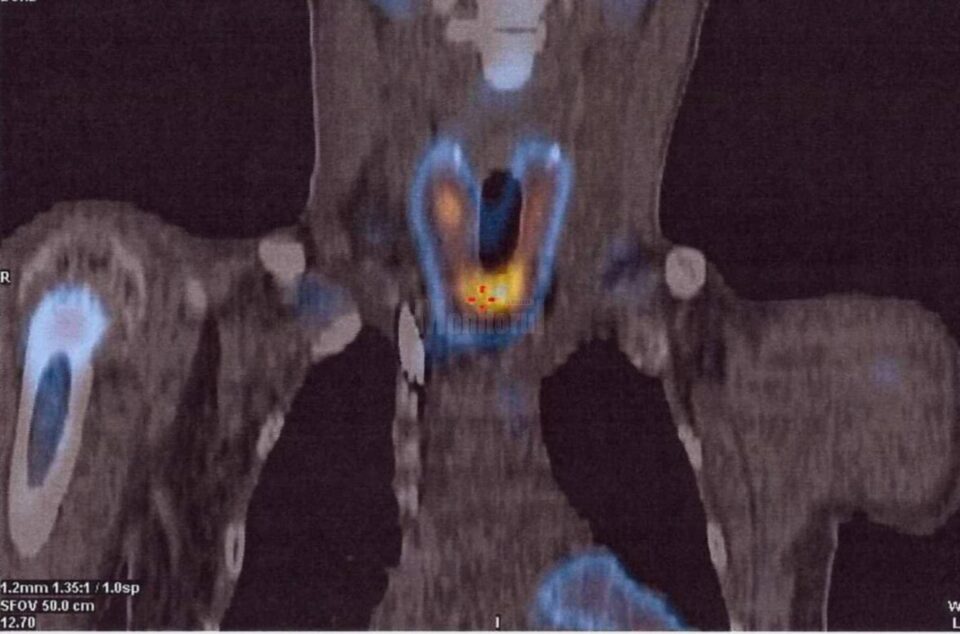

O echipă medicală multidisciplinară formată din dr. Rareș Voinea, dr.Mihaela Guțu, dr. Mihai Guțu, dr. Ionuț Cordoș, dr. Adrian Nistor și dr. Ruslan Gorceag a realizat o nouă premieră la Spitalul Județean de Urgență „Sfântul Ioan cel Nou” Suceava – prima paratiroidectomie subtotală (îndepărtarea unor porțiuni din glandele paratiroide), la un pacient în vârstă de 19 ani. Managerul spitalului, dr. Alexandru Calancea, a transmis, printr-un comunicat de presă, că pacientul a fost diagnosticat la sfârșitul anului 2020 cu boală cronică de rinichi, în stadiul terminal, și era inclus în programul de hemodializă. O complicație frecventă a acestei boli este creșterea glandelor paratiroide, ce determină modificări osoase. „Pe fondul acestora pacientul a prezentat o fractură spontană de col femural, rezolvată prin protezare de către medicul ortoped dr. Rareș Voinea”, a arătat dr. Calancea. Acesta a explicat că evaluarea glandelor paratiroide s-a realizat cu ajutorul medicinei nucleare, de către dr. Mihaela Guțu și dr. Mihai Guțu, prin SPECT-CT, identificându-se astfel cu exactitate locația și mărimea acestora. Ulterior, echipa chirurgicală, formată din dr. Ionuț Cordoș și dr. Adrian Nistor, a efectuat prima paratiroidectomie subtotală la Suceava. Pacientul a fost urmărit în continuare în secția de Anestezie Terapie Intensivă, sub coordonarea dr. Ruslan Gorceag, a mai spus dr. Alexandru Calancea.